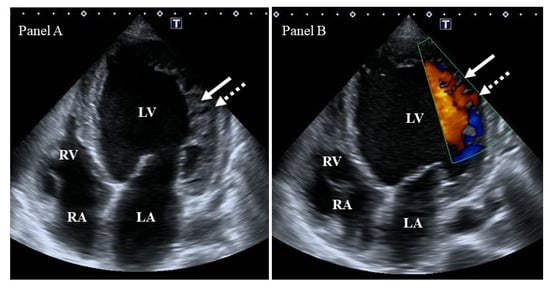

- Li, Q.; Miao, L.; Xia, L.; Abdelnasser, H.Y.; Zhang, F.; Lu, Y.; Nusrat, A.; Tabassum, M.; Li, J.; Wu, M. Left Ventricular Noncompaction Is Associated with Valvular Regurgitation and a Variety of Arrhythmias. J. Cardiovasc. Dev. Dis. 2022, 9, 49. [Google Scholar] [CrossRef]

| The prevalence and grades of MV regurgitation were higher. | [88] | 45 | |

| Patients showed a higher ratio of AV regurgitation. | [88] | 45 | |

| The prevalence and grade of TV regurgitation were higher. | [88] | 45 | |